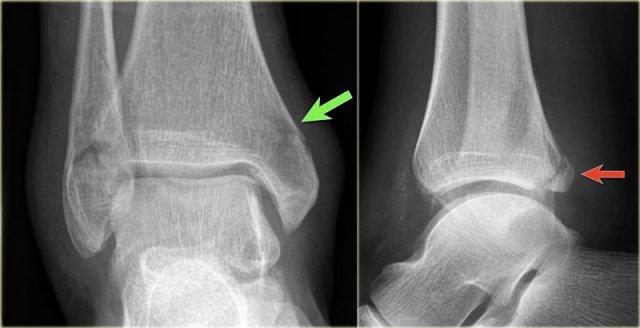

Hình ảnh X-quang cho thấy một gãy xương Weber B điển hình.

Hãy quan sát kỹ hình ảnh trước rồi tiếp tục đọc.

Bạn có nhận ra đây là giai đoạn nào không?

Đây là tổn thương Weber B giai đoạn 4.

Lưu ý rằng cả 4 giai đoạn đều có thể nhìn thấy:

- Đứt dây chằng chày mác trước – biểu hiện bằng sự giãn rộng khoảng cách giữa đầu xa xương chày và xương mác (khoảng sáng bên ngoài).

- Gãy xương mác chéo ở mức khớp chày mác – tức là gãy kiểu Weber B.

- Gãy xương Tertius – thấy trên phim thẳng (mũi tên đỏ) và trên phim nghiêng (mũi tên vàng).

- Rupture của dây chằng bên trong – được thấy như sự mở rộng của khoảng cách giữa mắt cá chân trong và xương sên (khoảng sáng trong)

Những hình ảnh này cho thấy một gãy xương Weber B điển hình giai đoạn 4.

Có một đường gãy chéo của xương mác.

Có một gãy giật bong mắt cá sau và một gãy giật bong mắt cá trong.

Đây là một trường hợp điển hình khác của gãy xương Weber B giai đoạn 4.

Đầu tiên, hãy chú ý đến đường gãy xương mác chéo, được thấy rõ nhất trên hình chiếu nghiêng.

Đây là giai đoạn 2 và chúng ta phải giả định rằng dây chằng khớp chày mác trước đã bị đứt.

Trên hình chiếu nghiêng, có thể thấy một mảnh vỡ nhỏ của cơ mác thứ ba, cho thấy giai đoạn 3.

Bây giờ bạn bắt đầu tìm kiếm giai đoạn 4 và sẽ nhận thấy vùng thấu quang mờ ở mắt cá trong trên hình chiếu thẳng (mũi tên xanh lá).

Dựa vào hiểu biết về các giai đoạn của Lauge Hansen, đây chắc chắn phải là một đường gãy xương.